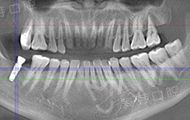

拍了片子,医生指出牙周膜增宽,左上根尖部阴影大,面部有稍微萎缩,为我制定了数字化精确种牙技术,其实也很好奇,现在种牙到底有多精确多快速,和医生约定好了时间,下次直接种牙。